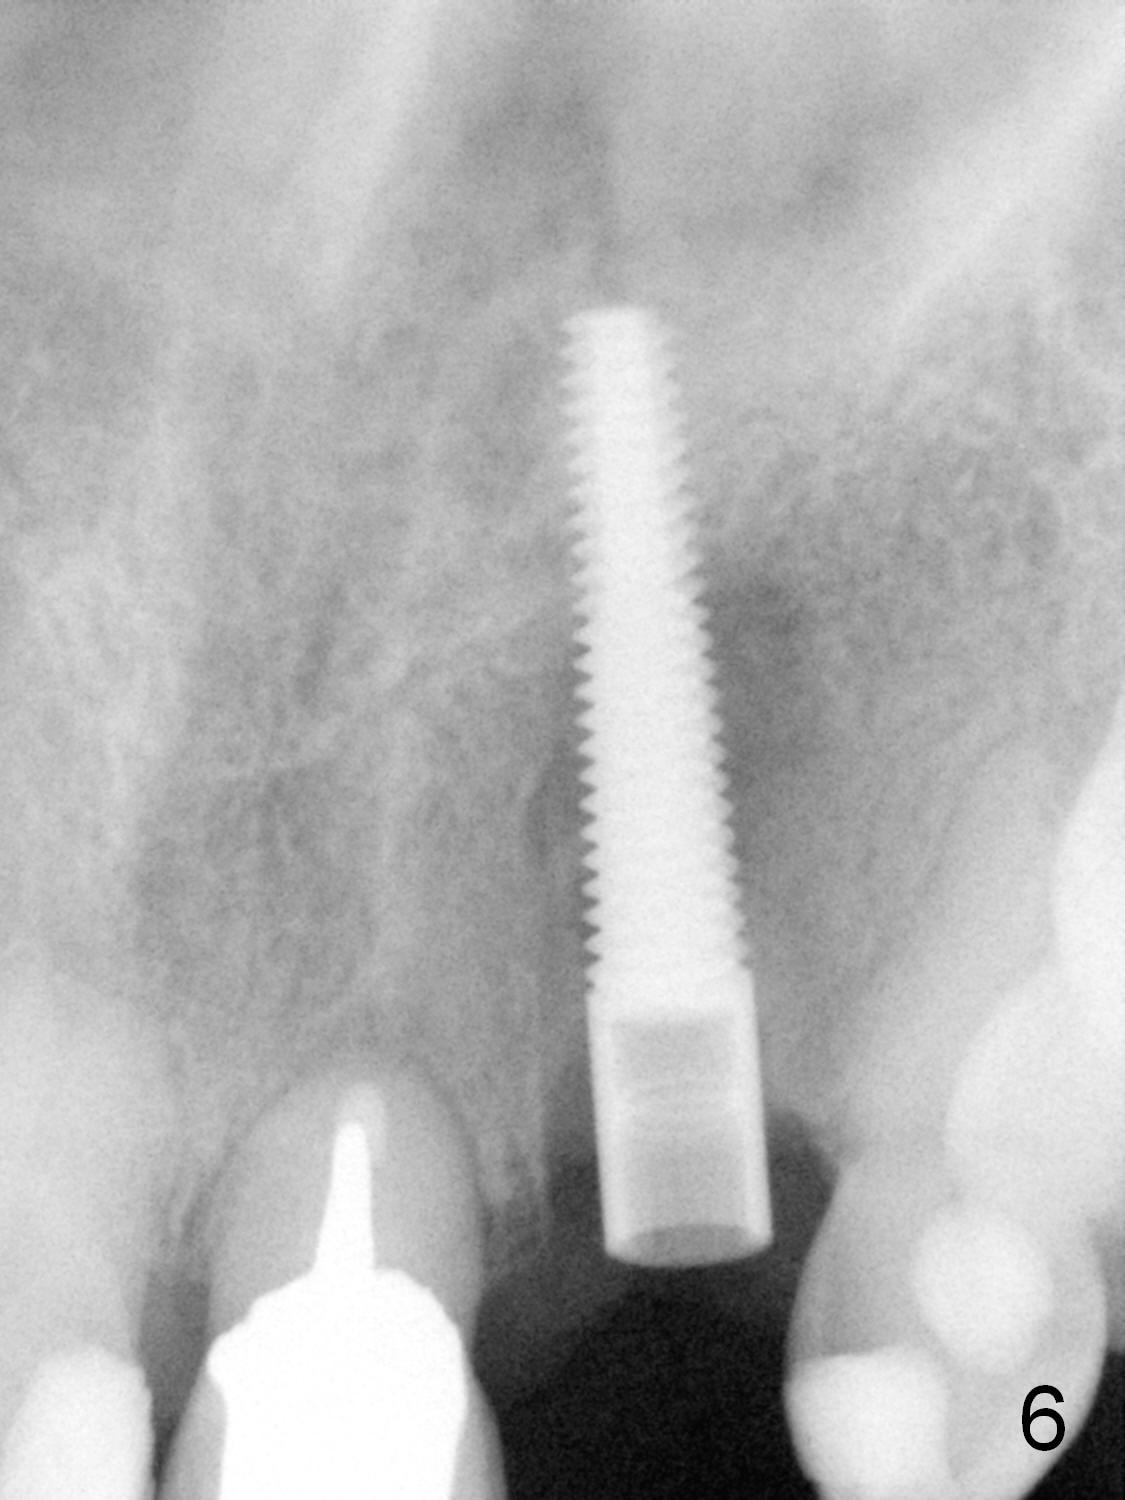

The 57-year-old lady does not like the crown at the site of #10 immediately when it is cemented (Fig.1). When the upper lip is retracted, it appears that the implant is immediately underneath the gingiva (Fig.2 *). It is slightly tender when palpated. The patient refuses CBCT. When the buccal flap is raised, the implant is found to be exposed buccally (Fig.3). When it is removed, the coronal portion of the palatal wall is thin (Fig.4). It appears that there is bone in the mid and apical thirds of the palatal wall, where an osteotomy is initiated using a 1.2 mm pilot drill. When the latter reaches 18 mm from the crest, the nasal floor appears to be perforated. The latter is confirmed by PA (Fig.5). As the osteotomy are increasing in diameter, force is applied as palatally as possible without perforating the palatal wall too much. When a 3.5x20 mm implant is placed (30 Ncm), it is palatal to the labial wall. The defect is filled by allograft and Osteogen, covered by long termed resorption membrane. The buccal flap is sutured (Fig.7). A proposal to place gingival graft is rejected. The implant is shown to have been positioned more or less normally (Fig.8). A removable temporary appliance is fabricated. Periodontal dressing is applied.